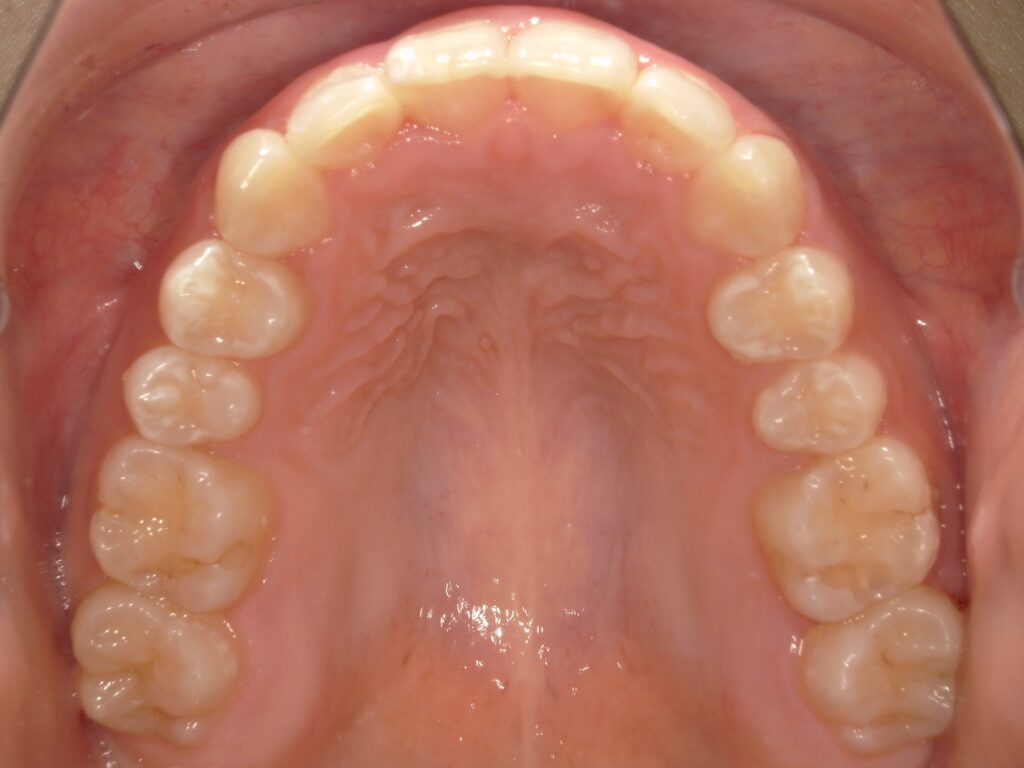

実際に顔に変化が起きた当院の症例を写真で紹介

こちらは当院で矯正治療を行い、患者様のご希望通りの顔貌の変化が起きた症例写真です。

BEFORE

AFTER

症例写真は一例であり、適応や結果には個人差がありますが、適切な診断と治療を行うことでこのような結果を出すことが可能です。